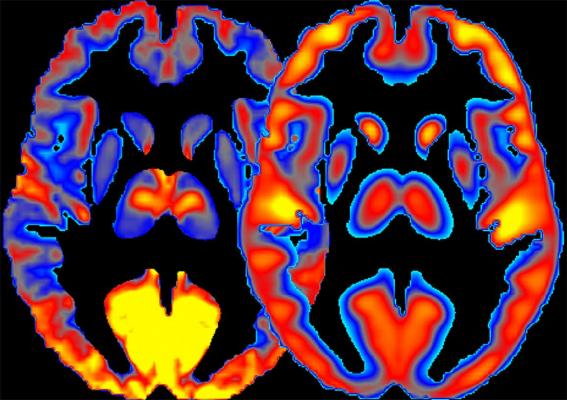

NIH scientists present a new method for combining measures of brain activity (left) and glucose consumption (right) to study regional specialization and to better understand the effects of alcohol on the human brain. Image courtesy of Ehsan Shokri-Kojori, Ph.D., of NIAAA.

In their new study, the researchers combined human brain imaging techniques, including FDG-positron emission tomography (PET) and magnetic resonance imaging (MRI), for measuring glucose metabolism and neuronal activity to derive new measures, which they termed power and cost.

“We measured power by observing to what extent brain regions are active and use energy,” explained Shokri-Kojori. “We measured cost of brain regions by observing to what extent their energy use exceeds their underlying activity.”

In a group of healthy volunteers, the researchers showed that different brain regions that serve distinct functions have notably different power and different cost. They then investigated the effects of alcohol on these new measures by assessing a group of people that included light drinkers and heavy drinkers and found that both acute and chronic exposure to alcohol affected power and cost of brain regions.